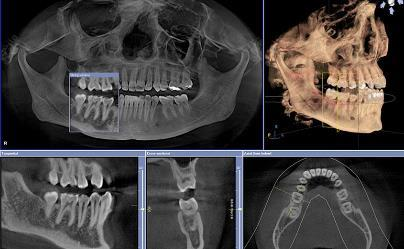

Cone Beam CT

Millions of people world wide have partial or complete edentulism. Dentures do not fully compensate patients adequately for tooth loss cosmetically or functionally. To address these issues dental implants are the accepted alternative. Dentists and oral surgeons will often initially assess their patients with x-ray. Dental CT programs offer more detailed and accurate information providing comprehensive preoperative assessment. Prior to performing this procedure, analysis of the bone of the mandible and maxilla is required in order to plan the appropriate implant procedure and limit surgical complications. The scanner allows for planning of dental implants by reconstructing the area of interest, identifying bone volume and vital nerves that need to be avoided. Excellent modality for bone detail and visualization of inner ear and paranasal sinusses. Low radiation dose especially useful in pediatrics.